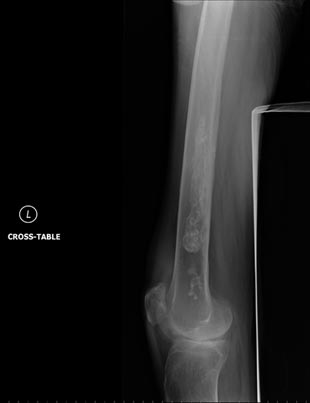

Radiografía del hueso largo en el muslo demuestra infartos calcificados en el hueso medular. Los pacientes con infartos medulares normalmente son asintomáticos.